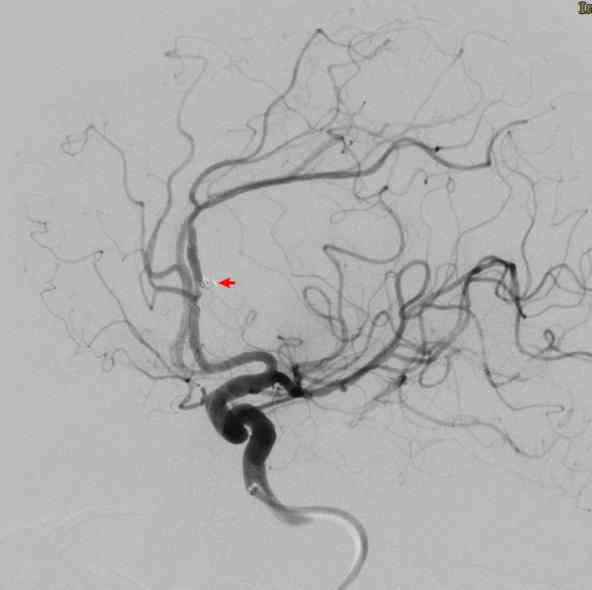

手术于复合手术室进行。先用血管造影机行CT检查提示脑室出血增多,脑室铸型,急性脑积水形成。团队立即行左侧脑室钻孔引流术,于左侧脑室内放置脑室引流管,颅内压极高,引流血性脑脊液。随后行脑血管造影提示左侧大脑前动脉A2段动脉瘤,团队采取微创治疗,应用支架辅助,于动脉瘤内填入3枚弹簧圈,造影显示动脉瘤完全闭塞,载瘤动脉通畅。手术历时3小时,手术完毕后行CT检查未见新发颅内出血,脑室引流管位置良好。

▲栓塞后